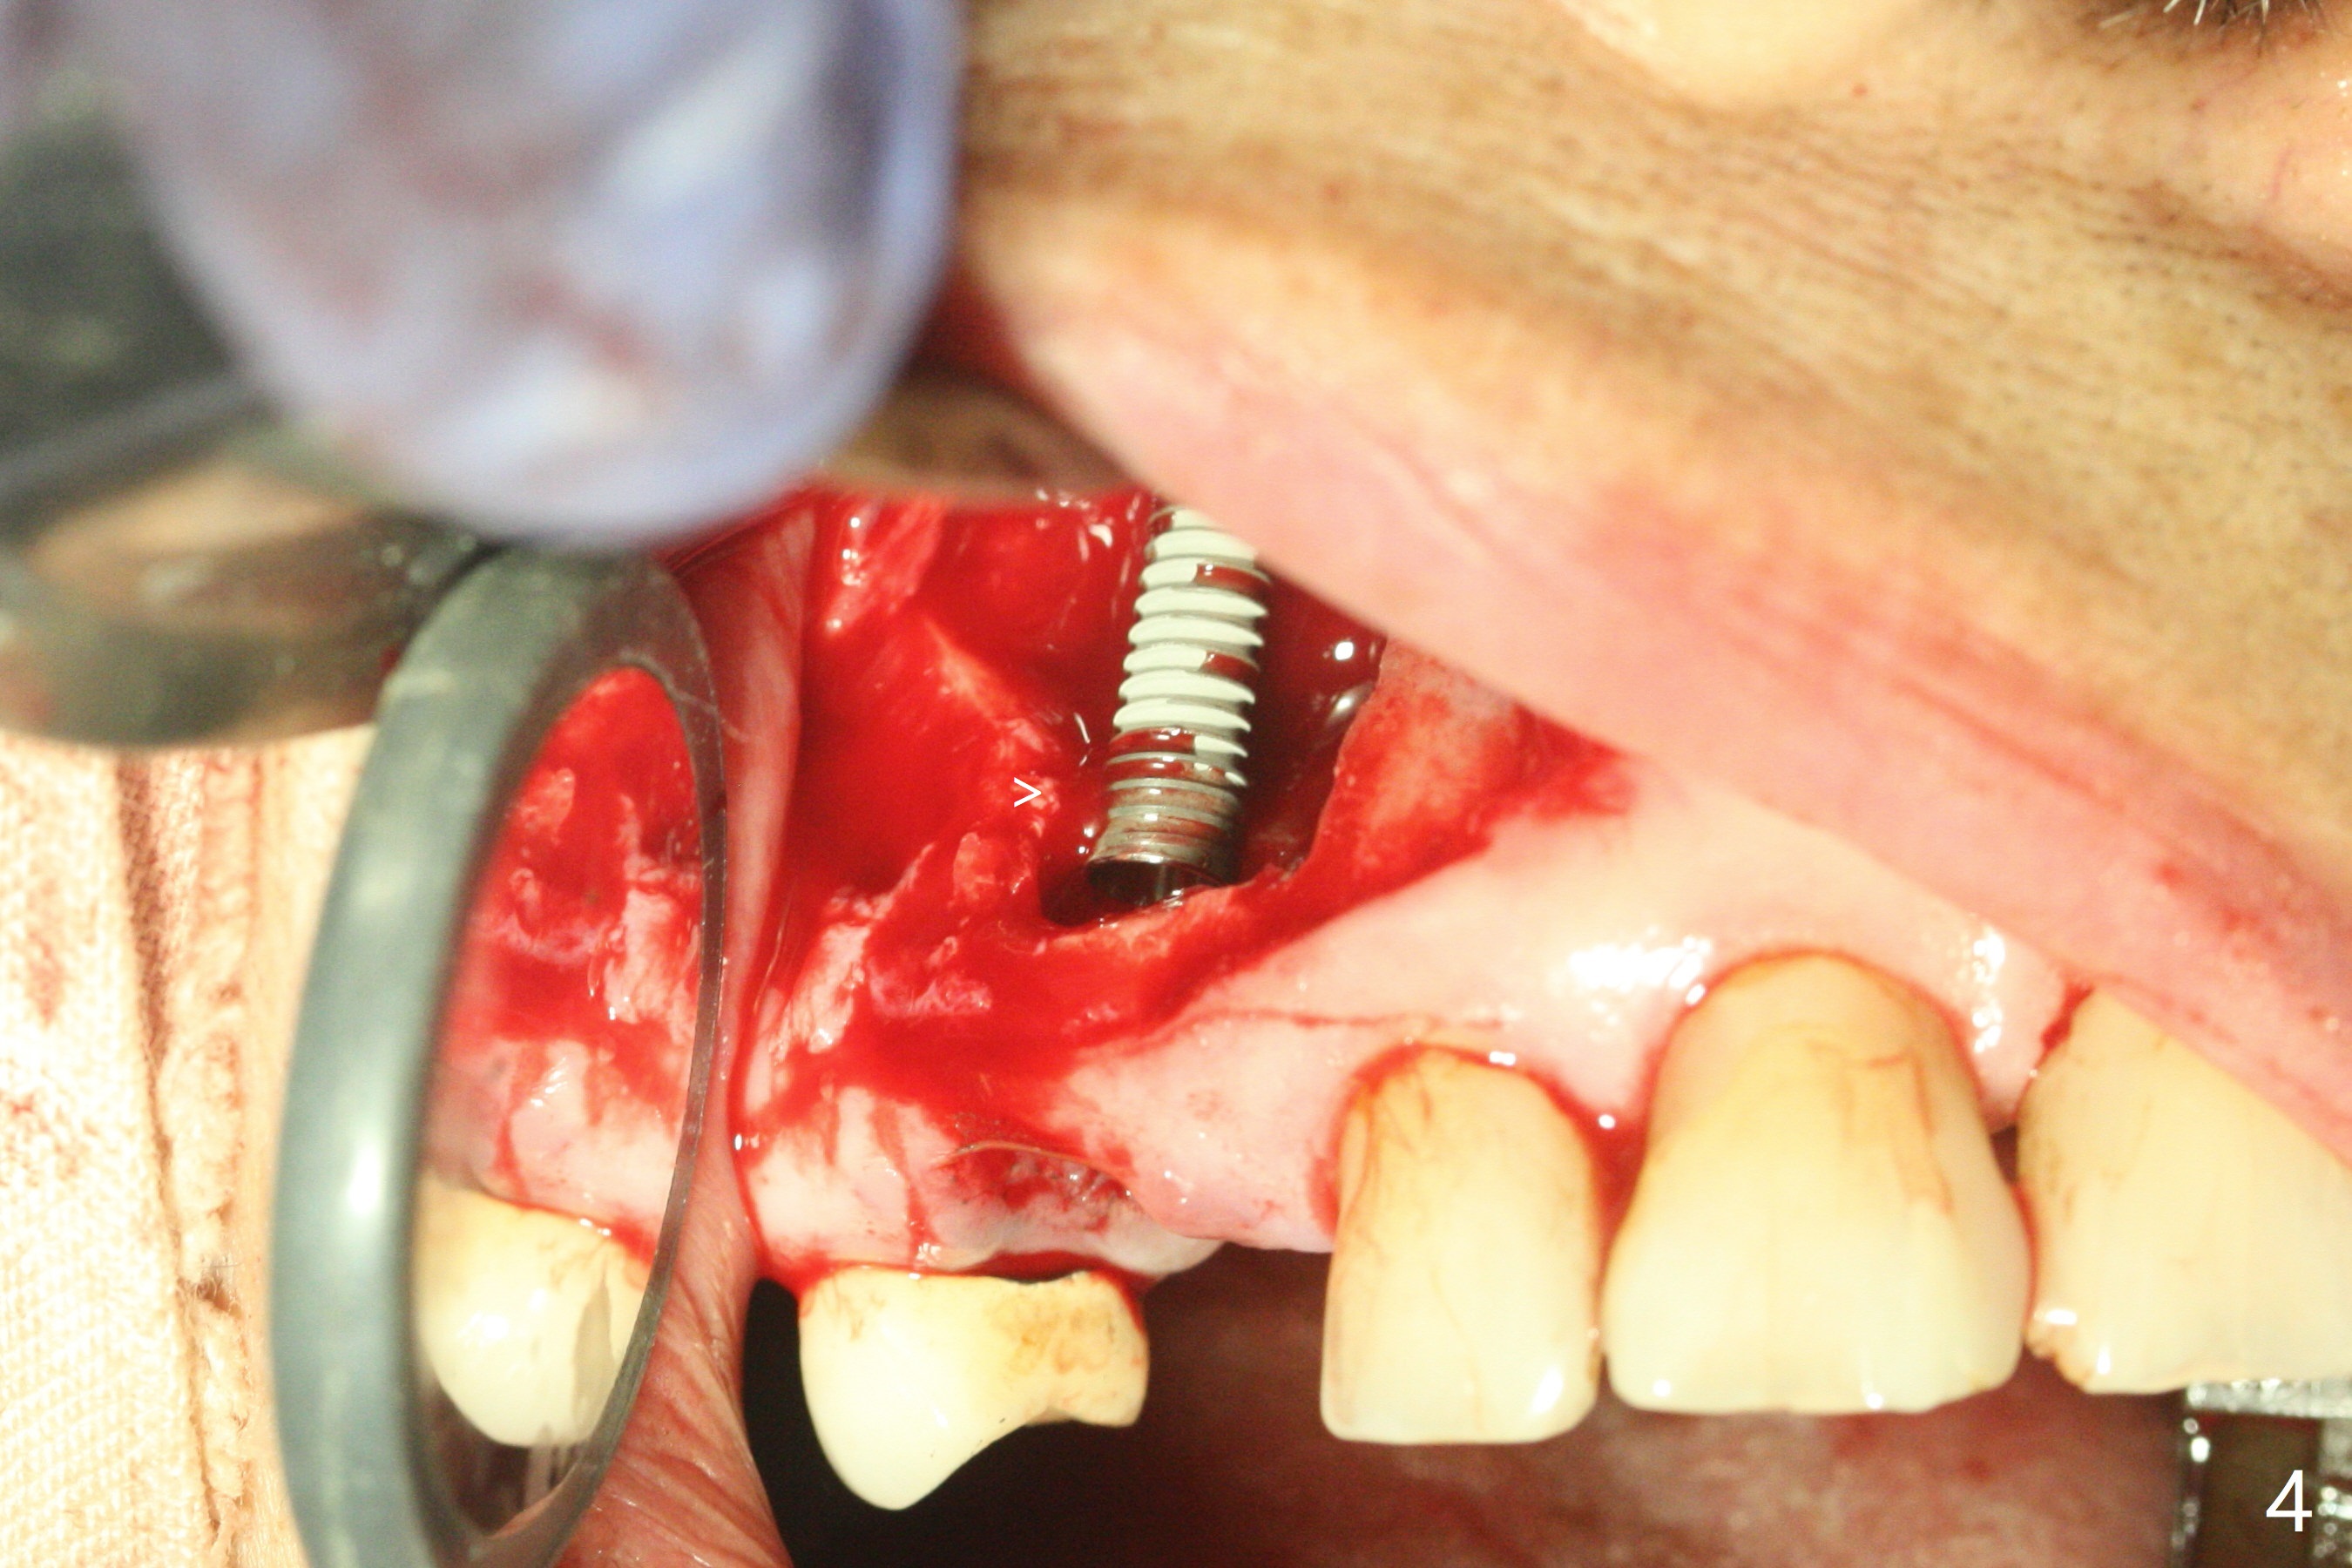

After incision and flap elevation, the crown of the impacted canine is more superficial. With removal of the buccal cortical plate and multiple sectioning of the crown, the latter is removed (Fig.1 *). Further removal of the buccal plate (P) and purchase points, the root (R) is extracted easier. In fact the apex of the root is the deepest (Fig.2). With the guide (Fig.3 G) and 2.2 mm drills, the osteotomy is established. It is pretty shallow. A 3x18 mm drill is used to deepen the osteotomy free hand (mistake: too palatal). When a 3.8x18 mm UF implant is being placed, it cannot be placed deep with the guide. When the latter is removed, the implant seems to be placed too deep and too buccal with <10 Ncm (Fig.4). A 4.5x7(5) mm abutment is placed mainly to correct the trajectory of the implant to certain degree. Placement of the implant at #3 is quite smooth (Fig.5) in spite of severe bone loss and abundant granulation tissue at #3 and 5. The implant at #5 does achieve 2 pointed fixation (Fig.4,6 arrowheads). The most coronal portion of the canine crown is left behind (Fig.6 C).